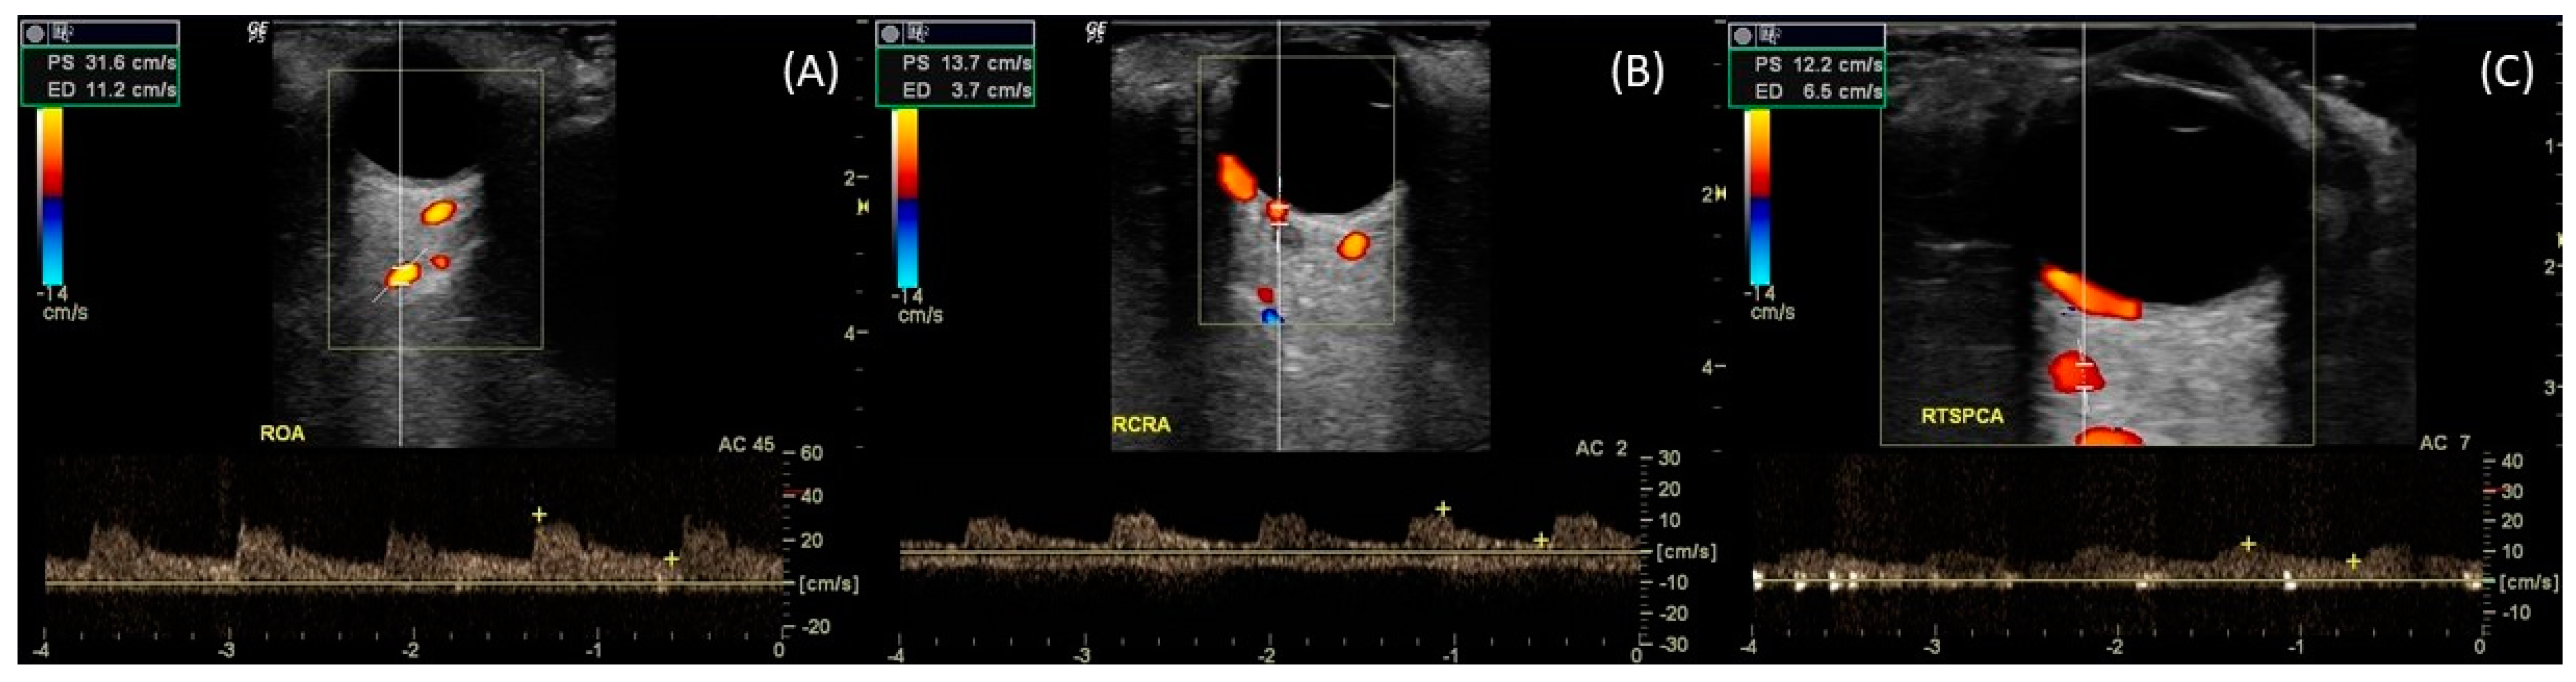

7. Color Doppler Imaging

7.1. CDI Principles

7.2. Doppler Waveform